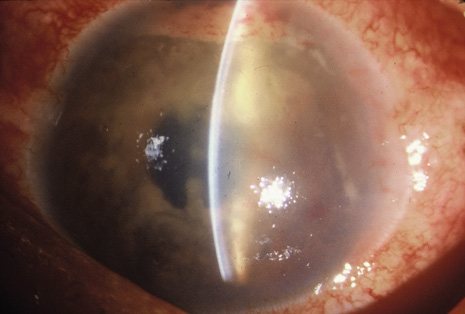

Although keratocentesis had been advocated historically as a treatment for active uveitis, it lost the attention of ophthalmologists until 1919, when Bruckner3 first examined the aqueous humor for diagnostic purposes. Laboratory techniques were revolutionized in the 20th century in areas such as: (a) evaluating very small aliquots of fluid (0.2 to 0.3 mL of aqueous or vitreous), and (b) identifying specific microbial organisms and the predominance of other cell types, antibodies, and proteins in these fluids (Figs. 1, 2, 3, 4, 5, and 6). These advancements have led to the development of diagnostic paracentesis for sight-threatening ocular inflammations that are difficult to diagnose. Witmer4 and O'Connor5 have provided strong evidence that samples of the aqueous humor reflect the antibody-producing capabilities of the iris and ciliary body, particularly when more specific antibody per unit of gamma globulin can be found on the aqueous humor than in the blood of the same patient.6–8 These determinations may be highly significant when one considers the fact that diseased tissue is being bathed in an antibody-containing fluid that is elaborated locally. For instance, in the case shown in Figure 1, the immunofluorescent antibody titer to toxoplasmosis is four times greater in the vitreous aspirate at the time of vitrectomy for repair of retinal detachment than in the plasma. These same considerations have long been recognized in syphilis of the central nervous system, wherein specific antibodies may be present in the cerebrospinal fluid but not in the blood. This is also the case with an unusual presentation of ocular coccidioidomycosis9 or toxocariasis.

Precise identification and culture of bacterial and fungal pathogens from both the aqueous humor and the vitreous fluid can be obtained. Gram's stain and Giemsa's stain smears of centrifuged specimens from the aqueous humor and the vitreous humor frequently demonstrate the bacterial or fungal causative agent. Attempts to isolate bacteria and fungi and to identify them on Gram's stain or Giemsa's stain smears have been most rewarding in the following cases: (a) postoperative endophthalmitis, (b) infection after a penetrating injury of the eye, (c) drug abuse patients with endogenous endophthalmitis (Figs. 21, 22, 23, 24, and 25), (d) patients receiving hyperalimentation, and (4) patients who are immunocompromised as a result of exogenous immunosuppressive agents.

Studies have demonstrated the usefulness of ocular paracentesis for the identification of ocular infections in order to implement sight-saving treatment.10–16 Even acid-fast bacilli and viruses may be diagnosed in this fashion when emergency dictates (see Fig. 5).17 It is recommended that diagnostic paracentesis be performed in all cases of postoperative endophthalmitis, and it is safe to perform the postoperative procedure in the operating room with the safety of vitrectomy surgery. Further, any patient older than 65 who presents with a deteriorating uveitis (usually with vitreitis as the predominant infiltrate) of undetermined etiology should undergo paracentesis of the vitreous to rule out reticulum cell sarcoma (large cell lymphoma).18 Similarly, any patient suspected of being an intravenous drug abuser who presents with an endogenous endophthalmitis or uveitis should undergo diagnostic paracentesis to avoid allowing an intraocular infection to be borne by the bloodstream.19,20